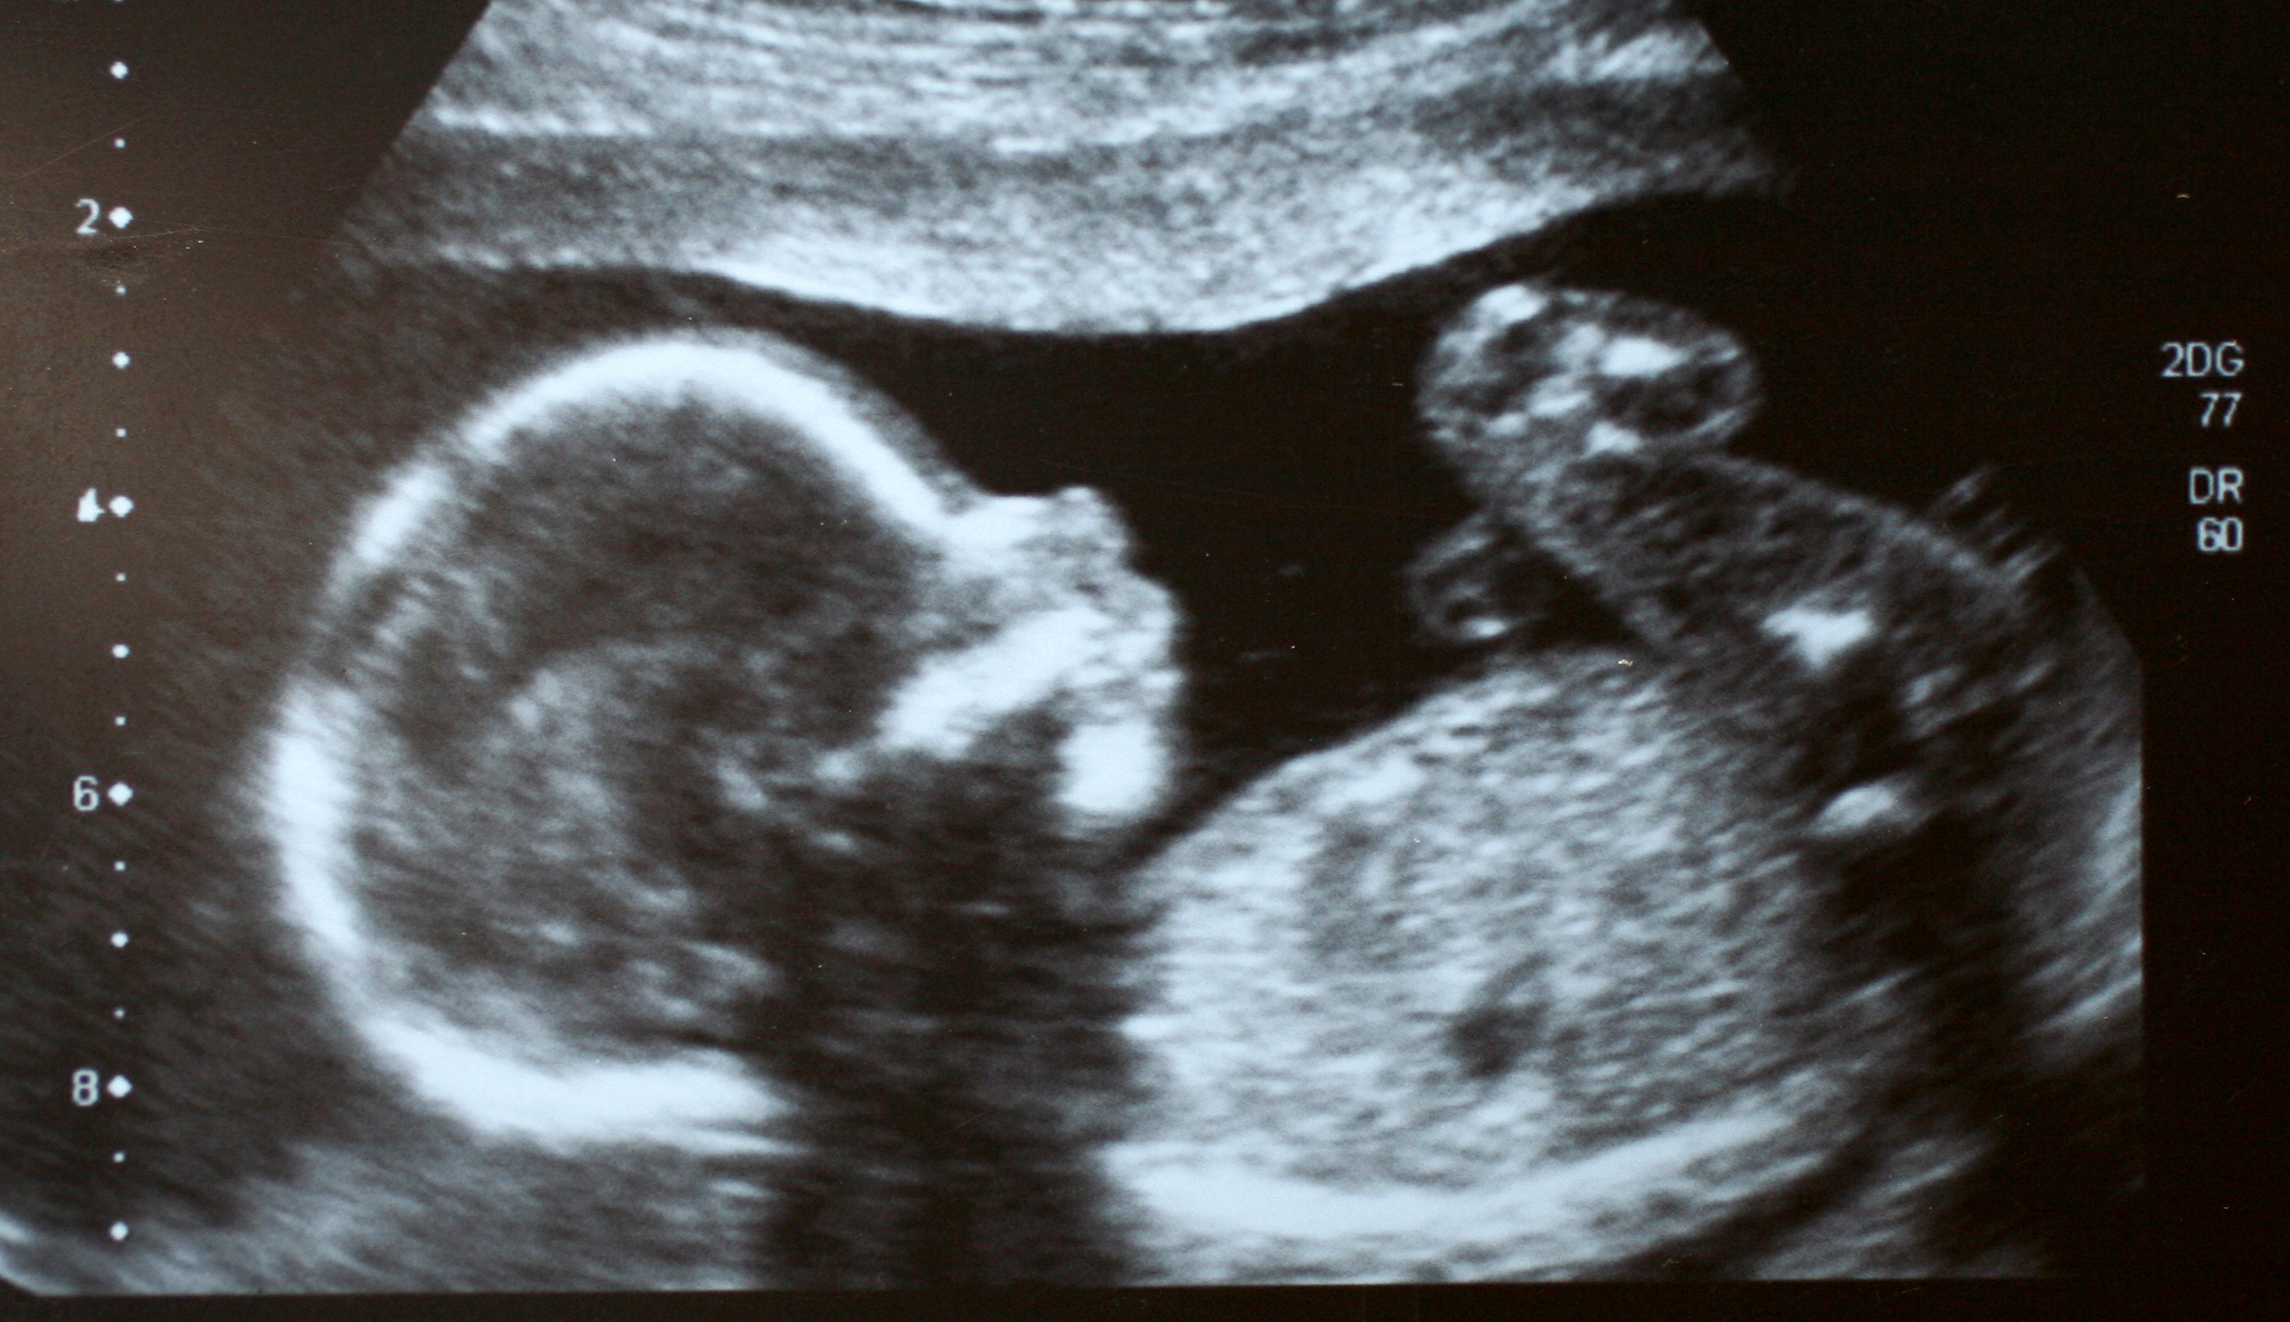

Vasectomies are not comparable to abortions in any real way. Sperm cells do not have their own unique DNA. They are gametes, reproductive cells that only carry half of the genetic code needed to create a human. Conception, when the sperm cell joins with a woman’s egg cell, creates a human being with its own unique genetics.

This is basic reproductive biology. You can find it in any biology or relevant medical textbook. If you were someone who simply “followed the science,” you would know this. But Democrats remain entirely unable to address the reality of what abortion is. They have to pretend that when life begins is a “belief” rather than a scientific reality. And that then leads to stunts by politicians such as Rabb, who respond to the strawman version of science that Democrats pretend the abortion debate is really about.